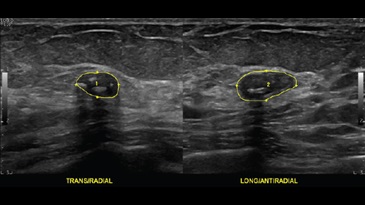

Доброкачественное образование в молочной железе с кальцинатами, ML6-15-D

Кисты в молочной железе, ML6-15-D